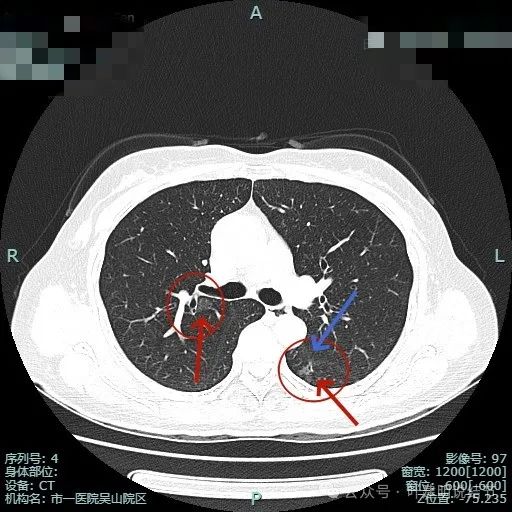

右上主病灶出现(病灶2),离肺门部非常近,密度较淡。

病灶1有明显叶间裂牵拉影响;病灶2密度虽淡,但轮廓清,贴着支气管壁。也有小血管走向病灶。